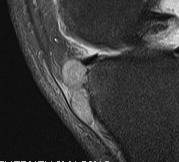

Popliteal Cyst / Baker's Cyst

Semimembranosus bursae or medial gastrocneumius

- can be herniation of synovium through capsule

- increases with fluid in the knee / OA / inflammatory conditions

- one way valve

Site

In midline and below joint line

- position crucial to avoid confusion with ST tumour

MRI

Diagnosis

- must communicate with knee joint